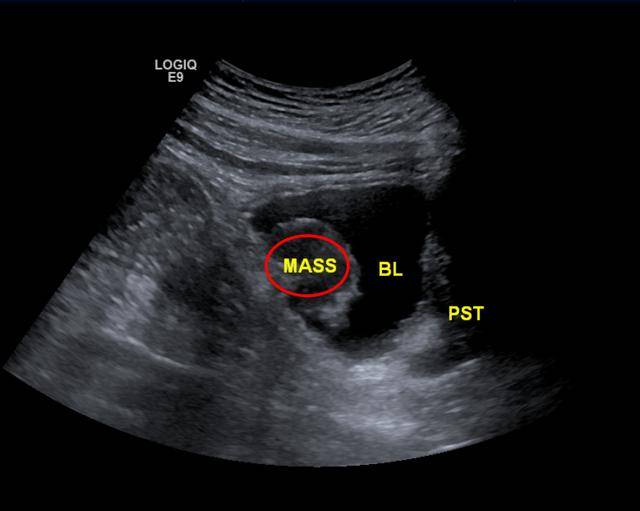

典型的膀胱癌一例